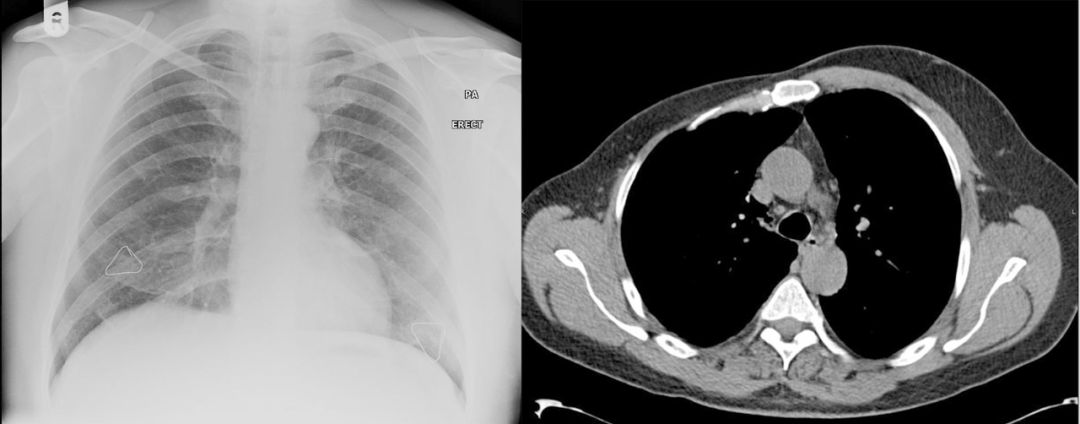

病例 3:左侧胸廓缩小,左侧胸大肌和胸小肌缺失,合并右位心

病例 4:胸部 X 线显示双侧乳头标记物高低不一致,右高左低,右肺野透亮度减低;右侧胸大肌及胸小肌缺失